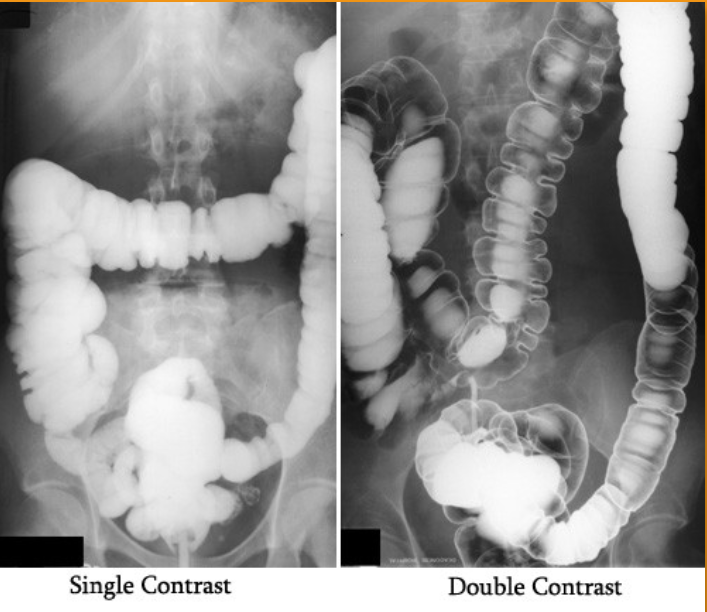

What contrast procedure was performed to produce this image?

Air-Contrast Barium Enema (ACBE)

1)What does single contrast mean in the first image?

2)What does double contrast mean in the 2nd image?

3)contrast media used for this examination?

4)the 3 contraindications of the contrast used?

1)entire colon is filled only with barium sulfate (this is a BE)

2)both barium sulfate and air. (this is a ACBE)

3)Barium Sulfate

4)DON’T us if suspected bowel perforation; Bowel obstruction (high risk of retention or perforation);

Pre- or post-surgy